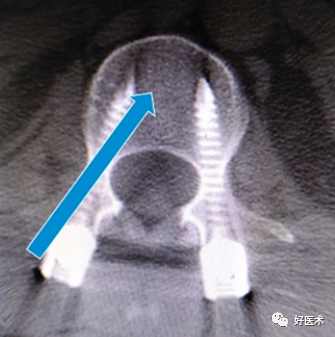

② 腰椎正位片子,猫眼是椎弓根椎狭窄部位的投影,按照操作手册,椎弓根螺钉偏内,容易损伤关节突关节面;

透视腰椎正位:上下终板成单边;椎弓根(猫眼)对称;棘突居中。

实际情况:没有专业的手术透视工作人员;正位和地面垂直;侧位和患者垂直;正位看猫眼内外,侧位看椎弓根上下。

判断:透视正位,椎管外的长度设定为A;透视侧位,椎体外的长度设定为B;如果A大于或者等于B,定位针不在椎管内;如果A明显小于B,定位针在椎管内。

透视结果(优秀):①正位:定位针在猫眼内;②侧位:定位针在椎弓根正中,和椎体轴向平行;③目标椎体正确。